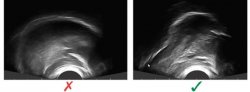

According to Hitchcock, McAllister and Preston, the use of acoustic and ultrasound biofeedback can significantly increase the accuracy of “r” pronunciation in children and adolescents, although few clinicians currently have access to this method as a means of speech sound intervention. Visual-acoustic biofeedback uses instrumentation to provide a real-time display of acoustic events such as formant patterns (Figure 1) and has been linked to positive outcomes in individuals with RSE who have not responded to previous intervention. Ultrasound biofeedback uses an ultrasound probe (Figure 2) – similar to ones used in cardiac and tissue imaging – which is held under the chin, and sound waves capture real-time images of the tongue. The images provide both the child and speech pathologist with information about the tongue’s position and shape.

Research suggests that visual biofeedback enhances the sensory experience of producing a sound like “r”. In addition to hearing the sound of speech, the child sees a visual display of her own speech and a model representing the correct pronunciation of the sound. The model creates a target. Using the visual display, the child can adjust her speech to achieve a better match with the target.

After a decade of testing these approaches with small scale studies, the research team has sufficient evidence to attribute the success of the treatment model to the unconventional approach it brings to the task of learning speech. In traditional methods, the clinician typically asks the child to imitate the “r” sound that they hear. However, many children who are unable to produce a clear “r” sound also have trouble hearing the difference between a clearly produced “r” and incorrect “r”. The theory is that biofeedback is successful because it bypasses that auditory channel. Even if the child can’t hear the difference between good and bad “r”, they can see whether they are matching the target on the screen. Matching the target lets them know if they are saying the “r” sound clearly.